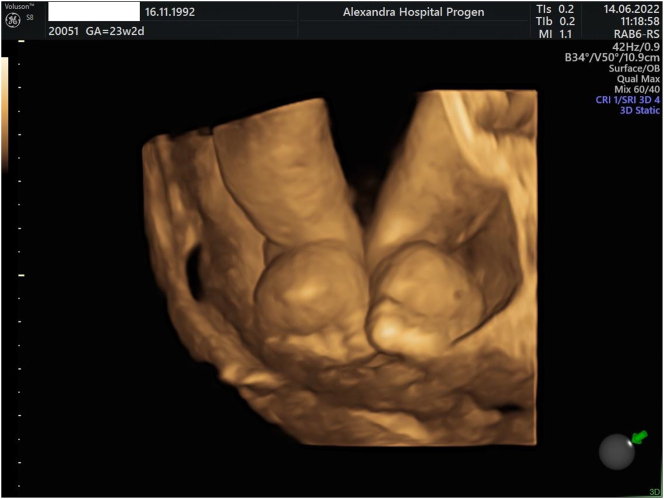

Case presentation: We present a case report of a first-described mutation of a male fetus diagnosed prenatally with Milroy syndrome through amniocentesis. The fetus had bilateral lower limb edema, and genetic testing confirmed the diagnosis of Milroy syndrome. The patient was closely monitored throughout the pregnancy, and after delivery, the infant was managed with appropriate therapies, including compression garments and manual lymphatic drainage. The parents were provided with appropriate counseling and support.

Abstract Image